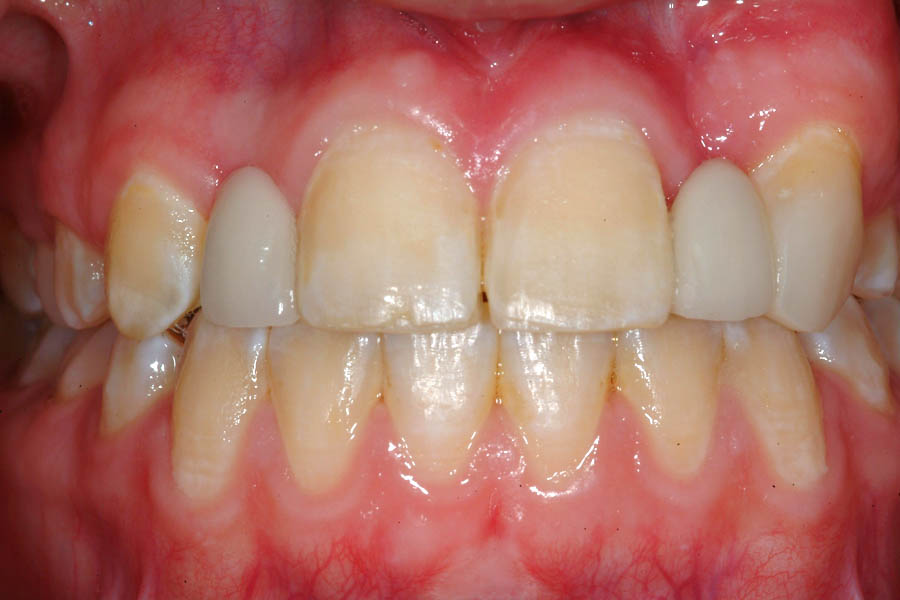

La momentul prezentării în clinică, în decembrie 2002, pacienta avea 8 ani şi o lună şi suferea de fibroză chistică şi de o deficienţă de dezvoltare a etajului mijlociu al feţei. Aceasta prezenta o anomalie de clasa I care mima o anomalie de clasa a III-a. Incisivii centrali, laterali şi caninii temporari maxilari, precum şi molarii prim şi secund de pe partea stângă erau în ocluzie inversă. În plus, pacienta prezenta coloraţii ale dinţilor de etiologie idiopatică (fig. 1). Autorii au considerat coloraţiile ca fiind de suprafaţă, extrinsece şi nu determinate de fibroza chistică, dovadă îndepărtarea acestora prin periaj profesional. Radiografia panoramică efectuată cu 6 luni înainte de prezentarea în clinica stomatologică relevă anodonţia incisivilor laterali superiori şi a premolarului secund drept inferior, ca şi posibila incluzie a caninilor maxilari, în special a celui stâng (fig. 2).

A doua etapă a tratamentului a fost amânată până în aprilie 2006, când pacienta a împlinit vârsta de 11 ani şi 5 luni. În acel moment, fetiţa prezenta erupţie şi dezvoltare radiculară adecvată, astfel că aparatele fixe aplicate acum n-ar fi purtate o perioadă îndelungată. Ocluzia inversă frontală şi angrenajul invers lateral fuseseră corectate; totuşi, exista o diastemă mare, în principal cauzată de lipsa incisivilor laterali superiori (fig.3). În acest moment, radiografia panoramică relevă anodonţia incisivilor laterali maxilari şi a premolarului secund drept mandibular, o anatomie redusă a rădăcinilor incisivilor centrali superiori, incluzia caninului superior stâng şi dezvoltarea întârziată a rădăcinii celui de-al doilea premolar inferior (fig. 4).

În aprilie 2009, după 37 luni de tratament, au fost îndepărtate aparatele fixe (fig. 6). Pentru contenţie, s-a aplicat un retainer fix colat pe faţa linguală a celor şase dinţi frontali inferiori şi o placă palatinală Hawley care încorporează dinţi acrilici în dreptul incisivilor laterali pentru a menţine un aspect estetic până când medicul protetician va putea realiza punţile dentare. În plus, s-a utilizat un arc vestibular care să consolideze contenţia şi care să permită aplicarea unor forţe uşoare, cu direcţie linguală, dacă este necesar.25 Croşetele ”în deget” sunt situate distal de incisivii centrali maxilari şi mezial de caninii superiori, pentru a permite o deplasare discretă mezio-distală a dinţilor, dacă este necesar (fig. 7).Înainte de îndepărtarea aparatului, a fost consultat medicul protetician. S-a pus problema dacă pacienta ar avea dificultatea de a purta pe termen lung un aparat mobil de contenţie, din cauza dificultăţilor de respiraţie şi a tusei, asociate cu fibroza chistică. În plus, din cauza anodonţiei de incisivi laterali superiori, osul alveolar este dezvoltat insuficient şi prezintă, astfel, dimensiuni prea reduse pentru inserarea implantelor dentare; procedura de augmentare a ţesuturilor moi şi dure ale crestei alveolare ar fi inevitabilă. Vârsta pacientei şi creşterea şi dezvoltarea corespunzătoare au fost, de asemenea, luate în considerare.19 Ortopantomograma finală relevă anodonţia molarilor de minte inferiori şi a celui superior drept pe lângă anodonţia incisivilor laterali maxilari şi a premolarului secund drept inferior. De asemenea, se remarcă aplatizarea rădăcinilor incisivilor centrali maxilari, care era prezentă şi pe radiografia efectuată înainte de tratament (fig.8).